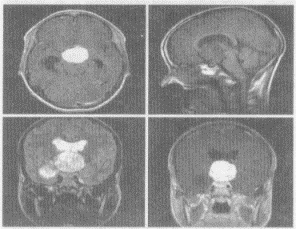

4.男,17岁,视力下降,头痛嗜睡4个月,MRI平扫及增强扫描,最可能的诊断为

正确答案:C